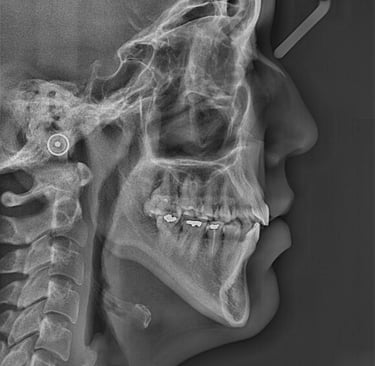

Durante las radiografías, se obtienen imagenes de los dientes y los huesos mediante rayos X.

Con motivo de una revisión dental, se toman radiografías interproximales (de aleta de mordida) según sea necesario. Se toman 1 o 2 de cada lado de la boca. Si tiene caries muy activas , puede que sean necesarias radiografías interproximales con mayor frecuencia. Estas radiografías se toman para detectar caries en los espacios interdentales y para comprobar el nivel óseo.

En las radiografías interproximales se puede observar el inicio de las caries antes de que sean visibles en la boca. Por lo tanto, es posible iniciar un tratamiento preventivo antes de realizar un empaste. Las radiografías interproximales también permiten evaluar el nivel óseo alrededor de los dientes y, por consiguiente, indicar si existe periodontitis.

En otros casos, puede ser necesario tomar una radiografía que abarque todo el diente. Estas radiografías se pueden utilizar, por ejemplo, para detectar caries o inflamación en el ápice de la raíz. Se toman, por ejemplo, antes de colocar una corona o en relación con un tratamiento de conducto.